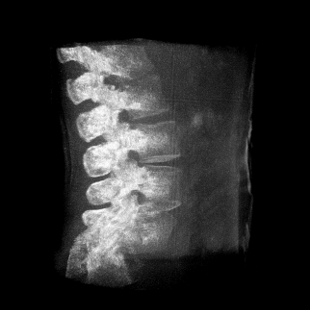

提供更大的術中三維成像視野,采集更多圖像信息,可一次拍全全段頸椎、全段腰椎、七節胸椎、雙側骶髂關節、股骨頭及單側盆骨。